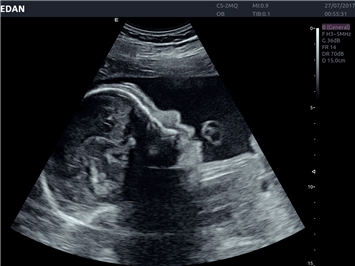

EDAN Acclarix LX4

Расширьте свои представления. Использование усовершенствованной платформой Acclarix система LX4 обеспечивает непревзойденную четкость изображений и интеллектуальный рабочий процесс для всех пользователей, являясь при этом наиболее экономичным решением.

EDAN Acclarix LX4 представляет собой инновационную ультразвуковую систему, построенную на усовершенствованной платформе Acclarix. Сочетание высокого качества визуализации с интеллектуальным рабочим процессом делает эту систему оптимальным выбором для клиник, ценящих эффективность и экономичность.

• 3D/4D-визуализация с автоматическим редактированием объема (eFace)

• Акушерства и гинекологии